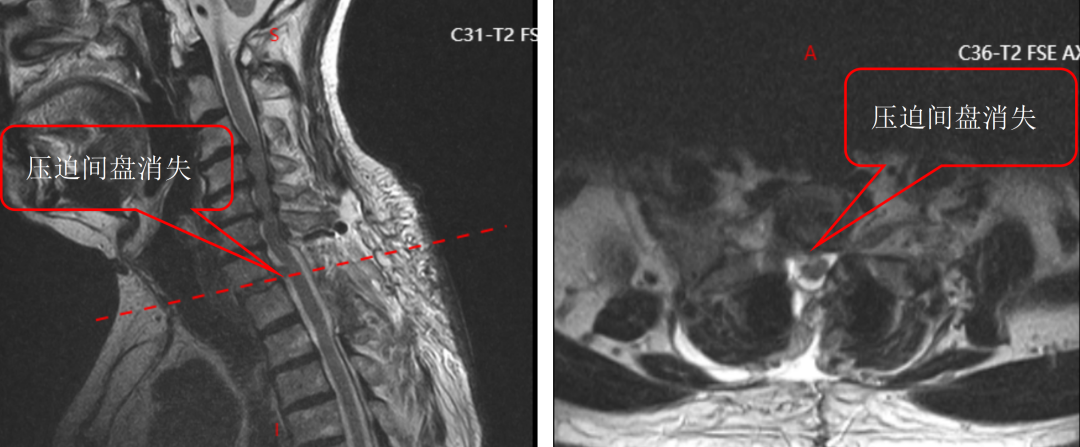

面对这一特殊情况,吴静晔主任没有急于下结论,而是为患者进行了细致全面的检查,最终精准诊断为脊髓型颈椎病。而进一步检查显示,患者存在C3-T1多节段狭窄,病情复杂且手术节段较多,这无疑给治疗带来了巨大挑战。

尤其是C7-T2椎弓根螺钉置入环节,传统手术极度依赖术中C臂透视,却因肩部遮挡,透视、定位极为困难,不仅手术视野受限、置钉难度陡增,螺钉还极易误入椎管,导致术中减压不充分,手术效果完全依赖主刀医生的丰富经验和精湛技术,是业内公认的“硬骨头”手术。